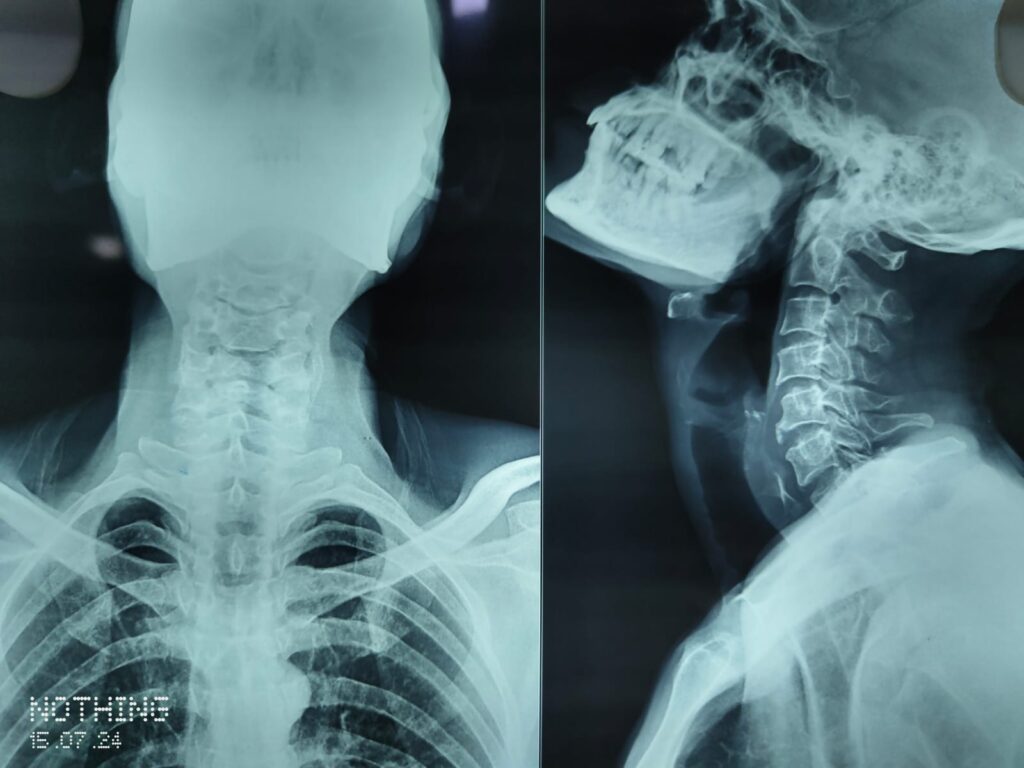

जिला चंबा में एक दुखद घटना सामने आई है, जहां ढाबे में खाना खाते समय गले में हड्डी फंसने से एक व्यक्ति की मौत हो गई। यह घटना चम्बा शहर के एक ढाबे में घटी, जिसके बाद क्षेत्र में शोक का माहौल है।प्राप्त जानकारी के अनुसार बीते कल 47 वर्षीय तरुण कुमार , पुत्र रवि कुमार, निवासी गांव मिंड़ा डाकघर हरदासपुरा, बीते कल करीब दोपहर 12 बजे शहर के एक ढाबे में अपने साथियों के साथ खाना खा रहे थे। इसी दौरान भोजन करते समय एक हड्डी उनके गले में फंस गई। हड्डी गले में अटकने के कारण उन्हें सांस लेने में परेशानी होने लगी।बताया जा रहा है कि तरुण कुमार ने गले में फंसी हड्डी को निकालने की काफी कोशिश की, लेकिन वह सफल नहीं हो सके। कुछ ही देर में उनकी हालत बिगड़ने लगी और वह बेहोश हो गए। ढाबे में मौजूद उनके साथी ने तुरंत उन्हें बेसुध हालत में उठाकर मेडिकल कॉलेज चंबा पहुंचाया, जहां डॉक्टरों ने जांच के बाद उन्हें मृत घोषित कर दिया।डॉक्टरों के अनुसार यदि उन्हें करीब दस मिनट पहले अस्पताल पहुंचाया जाता तो संभवतः उनकी जान बचाई जा सकती थी।

घटना की सूचना मिलते ही पुलिस की टीम भी मेडिकल कॉलेज चंबा पहुंच गई। वहीं मृतक के परिजन भी अस्पताल पहुंच गए, जिसके बाद माहौल गमगीन हो गया।पुलिस ने परिजनों के बयान दर्ज करने के बाद शव का फोरेंसिक विशेषज्ञ से पोस्टमार्टम करवाया। पोस्टमार्टम की प्रक्रिया पूरी होने के बाद शव परिजनों को सौंप दिया गया। पुलिस का कहना है कि मौत के सही कारणों का खुलासा पोस्टमार्टम रिपोर्ट आने के बाद ही हो पाएगा।हालांकि प्रारंभिक तौर पर यह माना जा रहा है कि गले में हड्डी फंसने के कारण तरुण कुमार सांस नहीं ले पाए, जिससे उनका दम घुट गया और उनकी मौत हो गई।पुलिस अधीक्षक विजय सकलानी ने मामले की पुष्टि करते हुए बताया कि ढाबे में खाना खाते समय व्यक्ति की मौत का मामला सामने आया है। पोस्टमार्टम रिपोर्ट आने के बाद पुलिस आगे की जांच प्रक्रिया को जारी